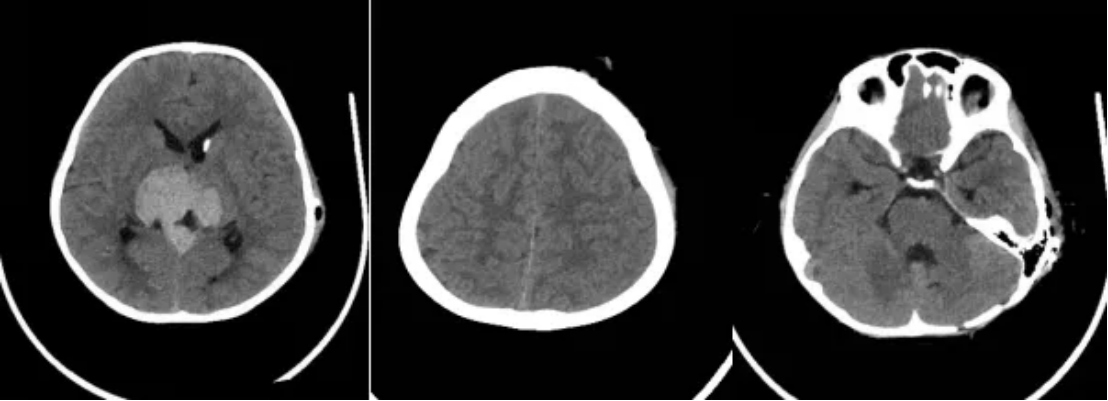

术后第一天(10月17日),患者体格检查显示,昏迷—嗜睡,双侧瞳孔D=3.0mm,光反应(+),CT检查结果提示脑积水缓解(图5)。术后血清和脑脊液肿瘤标志物检测(图6)、脑脊液细胞学检查和全脊髓MRI检查均为阴性。临床诊断为松果体区复发生殖细胞瘤,梗阻性脑积水。

图5 术后CT检查